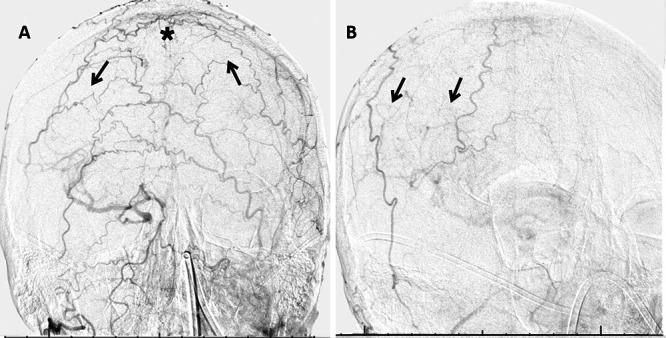

The patient had a good recovery with resolution of his preoperative symptoms. Follow-up angiography showed a patent bypass supplying the MCA territory through retrograde flow in the frontal and parietal limbs of the STA, converging at the anastomosis site. In this report, the authors present a new fourth-generation bypass dubbed the "S-S reverse STA-M4 MCA bypass."

患者恢复良好,术前症状消失。随访血管造影显示搭桥血管通畅,通过STA额支和顶支的逆行血流为MCA区域供血,在吻合部位汇合。在本报告中,作者展示了一种新的第四代搭桥术,称为“S-S反向STA-M4 MCA搭桥术”。